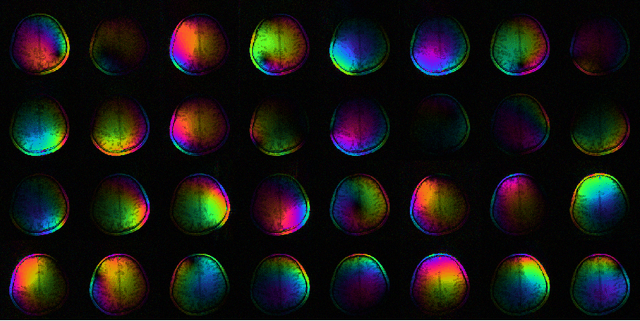

The main disadvantage of Magnetic Resonance Imaging (MRI) are its long scan times and, in consequence, its sensitivity to motion. Exploiting the complementary information from multiple receive coils, parallel imaging is able to recover images from under-sampled k-space data and to accelerate the measurement. Because parallel magnetic resonance imaging can be used to accelerate basically any imaging sequence it has many important applications. Parallel imaging brought a fundamental shift in image reconstruction: Image reconstruction changed from a simple direct Fourier transform to the solution of an ill-conditioned inverse problem. This work gives an overview of image reconstruction from the perspective of inverse problems. After introducing basic concepts such as regularization, discretization, and iterative reconstruction, advanced topics are discussed including algorithms for auto-calibration, the connection to approximation theory, and the combination with compressed sensing.